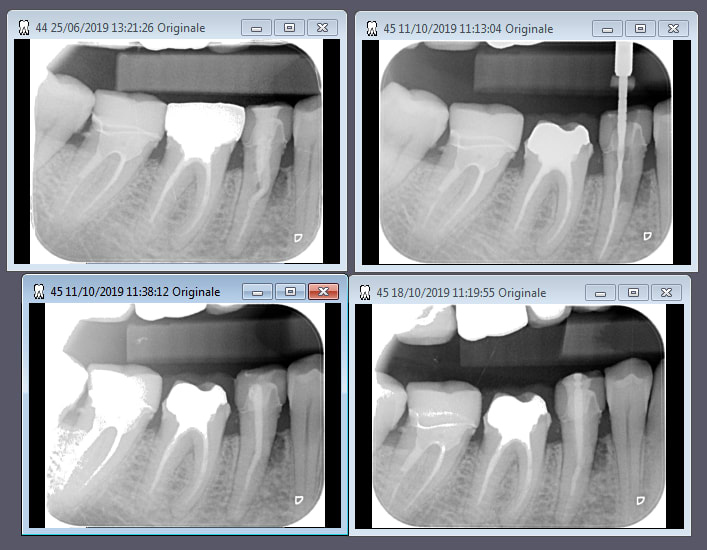

Oila, lapin et du coup un peu de temps pour poster le cas dont je parlais semaine derniere...

Coiffe zircone, necrose ou endo à revoir.... cavité d'acces a travers la coiffe et faux canal, resorption que sais je c'est pas moi qui avais commencé le cas.

En tout cas fistule en lingual...

Réouverture, je vire la gutta et la pâte, laser dans la raine, la chambre et sur les parois, laser depsui l’extérieur à travers la fistule.

Passage de limes jusque longueur de travail.

Une semaine interseance avec boulette de coton+He laurier noble.

Obturation avec biodentine "liquide" et un cone de gutta dedans histoire de me permettre de placer un tenon titane ensuite...

On a obturé y'a 10 jours, j'ai mis le tenon vendredi; ras depuis.

Du coup